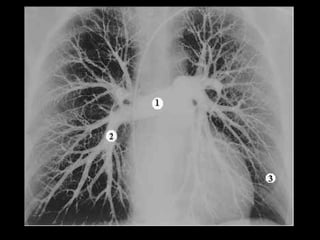

Exames de imagem: Rx Tórax

Primeiro passo na investigação radiológica da

suspeita de HAP;

Achados típicos: aumento do calibre das artérias

centrais, com rápido afilamento dos vasos à medida

que progridem para a periferia;

A área cardíaca pode estar aumentada ou normal;

Calcificação vascular: associado a alta RVP;

Sensibilidade baixa;

Útil para afastar ou sugerir causas de HAP;

Radiografia de tórax normal